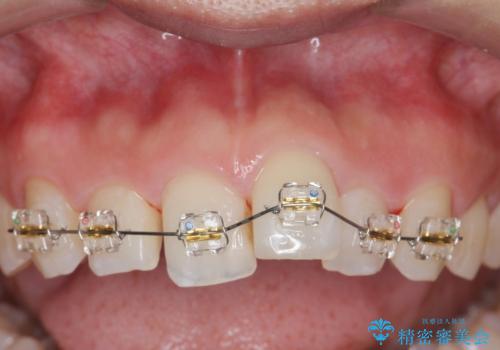

- 「前歯のガタつきをきれいにしたい。」と矯正治療を希望され来院されました。

前歯のガタつきをワイヤー部分矯正、上顎前突の咬合関係を後方移動することで理想的な咬合関係を確立します。

上顎の全体的な後方移動を実現するためにマイクロインプラントを併用したゴムかけを行ったことで理想的な咬合関係を確立することができました。